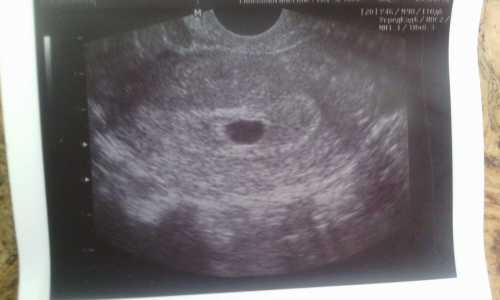

Но самой явной причиной отслойки плодного яйца является недостаток прогестерона, который часто называют гормоном беременности. Если у беременной женщины проявляются признаки отслойки плодного яйца, она или родственники должны срочно вызвать скорую и позвонить акушеру гинекологу, чтобы сообщить ему о случившемся. Пока бригада скорой помощи не приехала, женщина должна лечь, а ноги поднять кверху. Можно упереть их о стену или положить на спинку дивана. Отслойка плодного яйца опасна тем, что может привести к аборту или замершей беременности. Поэтому при малейшем подозрении на отслойку, нужно обратиться за медицинской помощью. На очень раннем сроке зародыша в плодном яйце еще не видно, и это норма. А вот с пяти недель эмбрион уже должен визуализироваться. В случае, если эмбриона не видно, через недели назначают повторное исследование.

УЗИ показало, что плодное яйцо меньше нормы в раза. Не могут срок сказать.